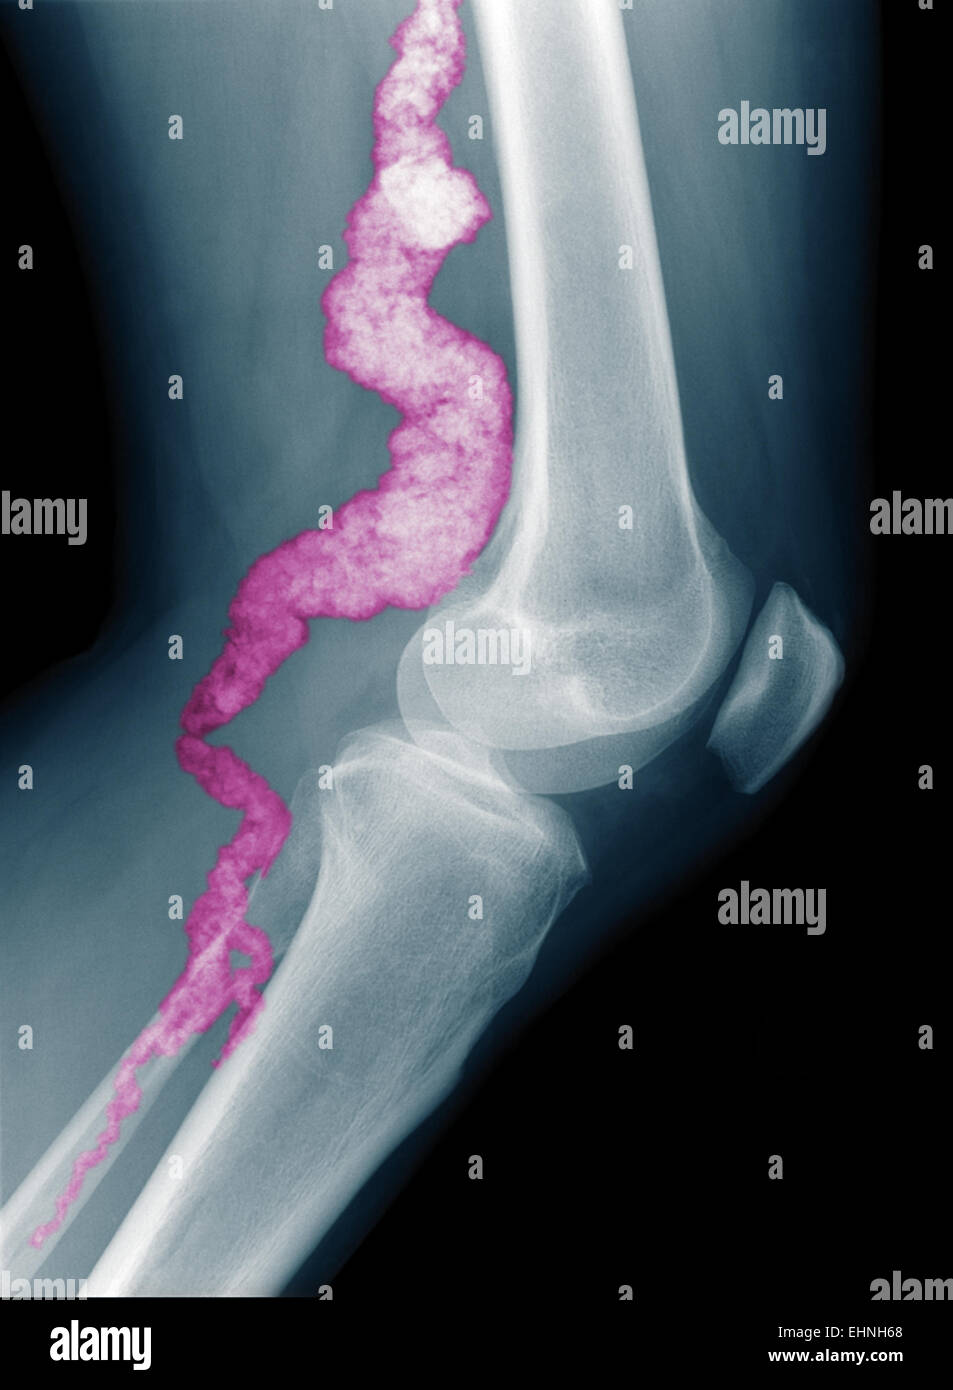

From www.alamy.com

Calcification artery hires stock photography and images Alamy Calcified Plaque In Leg Arteries Claudication is usually a symptom of peripheral artery disease, in which the arteries that supply blood to the arms or legs, usually the legs, are narrowed. Initial iterations were largely ineffective for heavily calcified lesions but later versions of the device (turbohawk) have incorporated changes to the. This makes it harder for your blood. The narrowing is usually due to. Calcified Plaque In Leg Arteries.

From radrounds.com

Monckeberg Medial Sclerosis and Popliteal artery aneurysm (XRay Calcified Plaque In Leg Arteries This makes it harder for your blood. Peripheral artery disease, or pad, is an accumulation of plaque (fats and cholesterol) in the arteries in your legs or arms. The prevalence of arterial calcification increases with. Medial artery calcification is associated with lower limb amputation in patients with diabetes and/or peripheral artery disease. If a piece of plaque. Claudication is usually. Calcified Plaque In Leg Arteries.